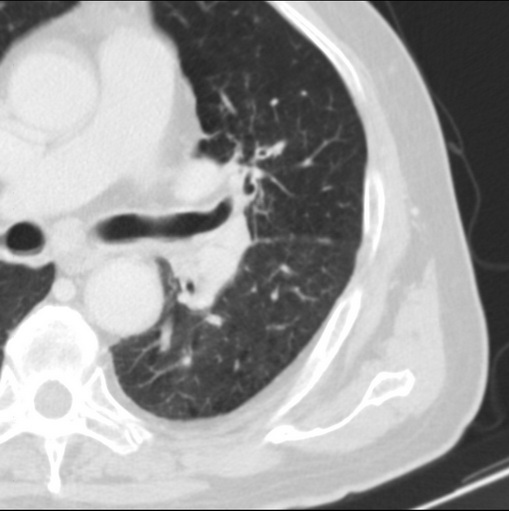

标题: CT25434:胸部CT增强扫描

男性患者 81岁 咳嗽 咳痰 咯血

左肺中心型肺癌并:1.左肺阻塞性肺炎;2.纵隔淋巴结肿大;

考虑左上肺癌并阻塞性肺炎,左肺转移、左肺门及纵隔淋巴结转移。

肿块贴近左肺门,包绕左上肺动脉,形态不规则。肿块增强扫描中度强化。纵膈内主动脉弓左旁间隙、气管隆突前、下间隙见多枚淋巴结影。综上考虑左侧中央型肺癌可能性大。图片没有完整上传,尤其是左肺上叶支气管分支层面没有上传,因此不好判断是叶支气管中断还是段支气管中断。另外,下图红色部分所示是“黏液支气管征”吗?